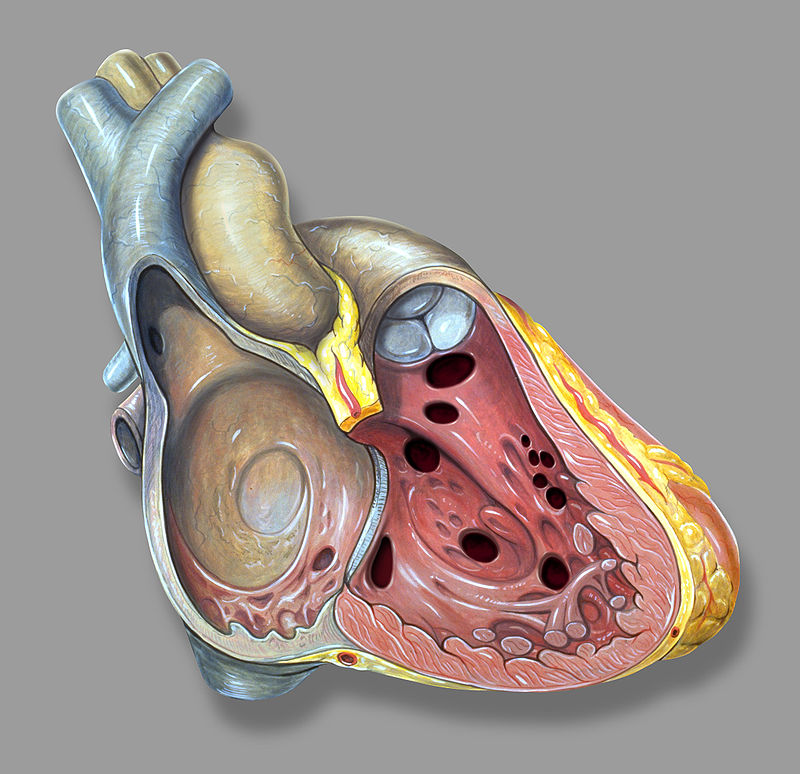

Congenital Heart Defects

Congenital heart defects occur throughout embryogenesis (usually weeks 3 through 8).

Congenital heart defects are observed in 1% of live births.

Most congenital heart defects are incidental and not clinically significant.

Congenital heart defects frequently cause shunting between the right (pulmonary) and left (systemic) circulations.

The shunt can gradually reverse, even though defects with left-to-right shunting may be largely asymptomatic at birth.

Pulmonary hypertension and pulmonary hypertrophy are caused by increased flow via the pulmonary circulation.

The shunt gradually reverses due to increased pulmonary resistance, causing late cyanosis (Eisenmenger syndrome) along with right ventricular hypertrophy, polycythemia, and clubbing.

Cyanosis is typically the first sign of right-to-left shunting defects soon after birth.